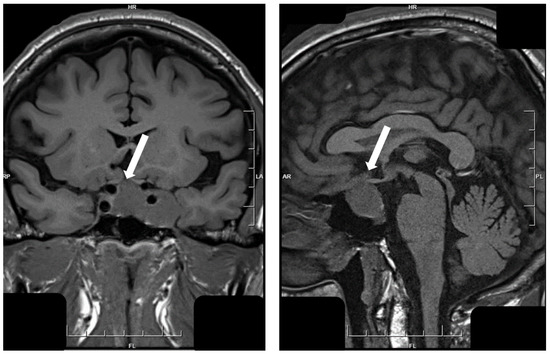

- Asa, S.L.; Kucharczyk, W.; Ezzat, S. Pituitary acromegaly: Not one disease. Endocr. Relat. Cancer 2017, 24, C1–C4. [Google Scholar] [CrossRef] [PubMed]

- Heck, A.; Ringstad, G.; Fougner, S.L.; Casar-Borota, O.; Nome, T.; Ramm-Pettersen, J.; Bollerslev, J. Intensity of pituitary adenoma on T2-weighted magnetic resonance imaging predicts the response to octreotide treatment in newly diagnosed acromegaly. Clin. Endocrinol. (Oxf.) 2012, 77, 72–78. [Google Scholar] [CrossRef]

- Potorac, I.; Petrossians, P.; Daly, A.F.; Alexopoulou, O.; Borot, S.; Sahnoun-Fathallah, M.; Castinetti, F.; Devuyst, F.; Jaffrain-Rea, M.L.; Briet, C.; et al. T2-weighted MRI signal predicts hormone and tumor responses to somatostatin analogs in acromegaly. Endocr. Relat. Cancer 2016, 23, 871–881. [Google Scholar] [CrossRef] [PubMed]